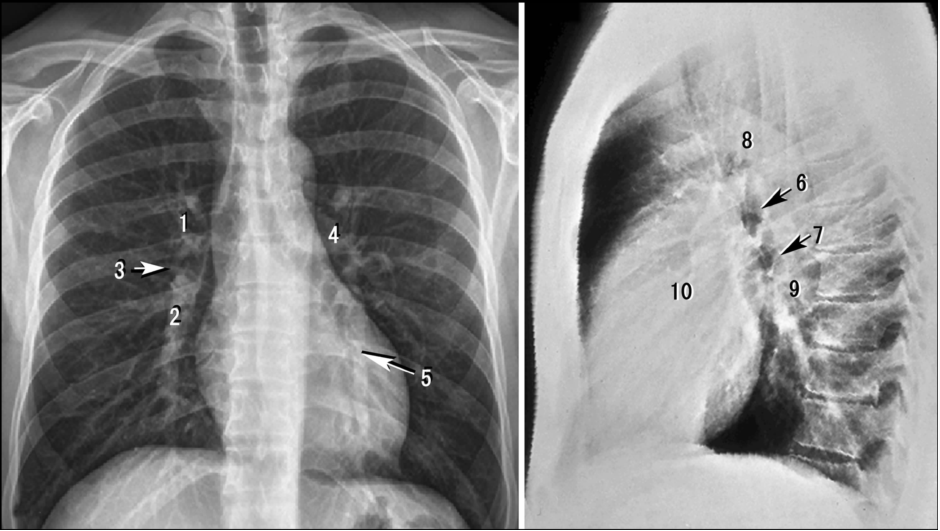

一、掌握胸廓和膈的正位和侧位X 线解剖。

二、掌握肺野、肺门、肺纹理、肺叶和肺段的 X 线解剖,了解胸膜的 X 线解剖,熟悉胸部X 线平片变化的主要因素。